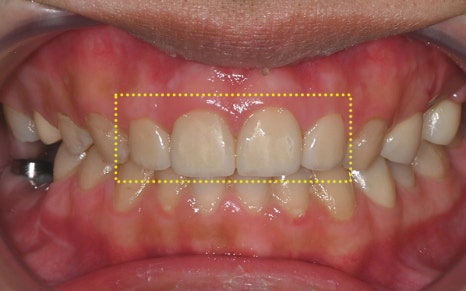

💛 Aesthetic Restoration of the Front Teeth 💛

This is what it looked like after some of the treatment had been completed.

The most noticeable change was,

above all, the aesthetic restoration of the front teeth.

Looking at the before-treatment photos,

the front teeth had large cavities and damage

to the point that it was hard to smile,

and the areas filled with resin here and there

were also a major source of aesthetic stress.

But the post-treatment photos

feel like a completely different person.

As if the teeth had originally been pretty and straight,

the color looks natural,

and the shape was restored to fit the face perfectly.

In fact, the patient said,

“This really feels like my original tooth,

and it doesn’t look like I had any treatment at all,” and expressed satisfaction.